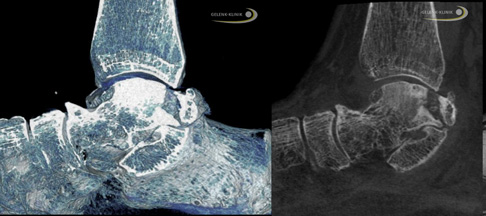

Besonders hilfreich für die Untersuchung von Knochenveränderungen sind Schnittbildverfahren, die mit Röntgenstrahlung arbeiten. Neben dem Kernspin (MRT) und SPECT ist besonders die digitale Volumentomographie (DVT) des Sprunggelenks wertvoll, um die charakteristischen Veränderungen im Innern des Sprungbeins darzustellen.

Nach einem Kollaps des Knochens unter dem Gelenkknorpel (subchondraler Knochen) kann nur das DVT (digitale Volumentomografie) die genaue Lage und Belastung der Knochenstrukturen darstellen. Das Röntgenbild als Überlagerungsbild ist ebenfalls eine gute Möglichkeit, die häufig aber – anders als die hochauflösende röntgenbasierte Schnittbilddiagnostik wie DVT oder CT – nicht die gesamte Situation der Strukturen darstellt. Daher ist ein Röntgenbild für eine Therapieentscheidung oft nicht ausreichend.